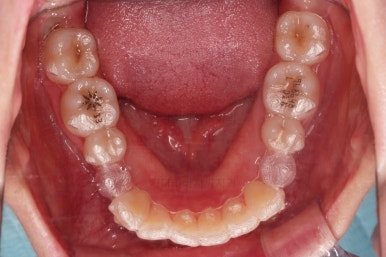

마찬가지로 초진 시 입안의 모습인데요.

전반적으로 약간 삐뚤지만 특히 윗니 앞니가 삐뚤고요.

송곳니는 덧니처럼 튀어나와 보이네요.

그리고 전반적으로 치아가 앞쪽으로 경사되어 있어서 앞니는 뻗친 느낌이 있네요.

가지런하게 하면서 앞니를 뒤로 당겨줘야 여러 가지 문제점들이 개선되기 때문에 발치교정을 했어요.